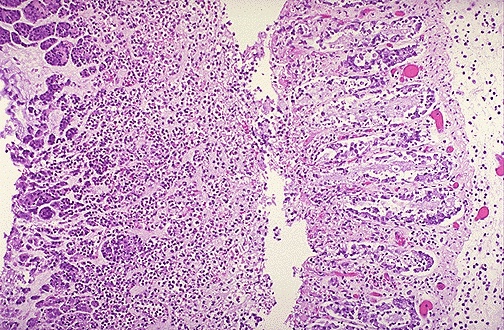

At high power microscopically, the colon shows surface mucosal erosions with overlying fibrinopurulent exudate.